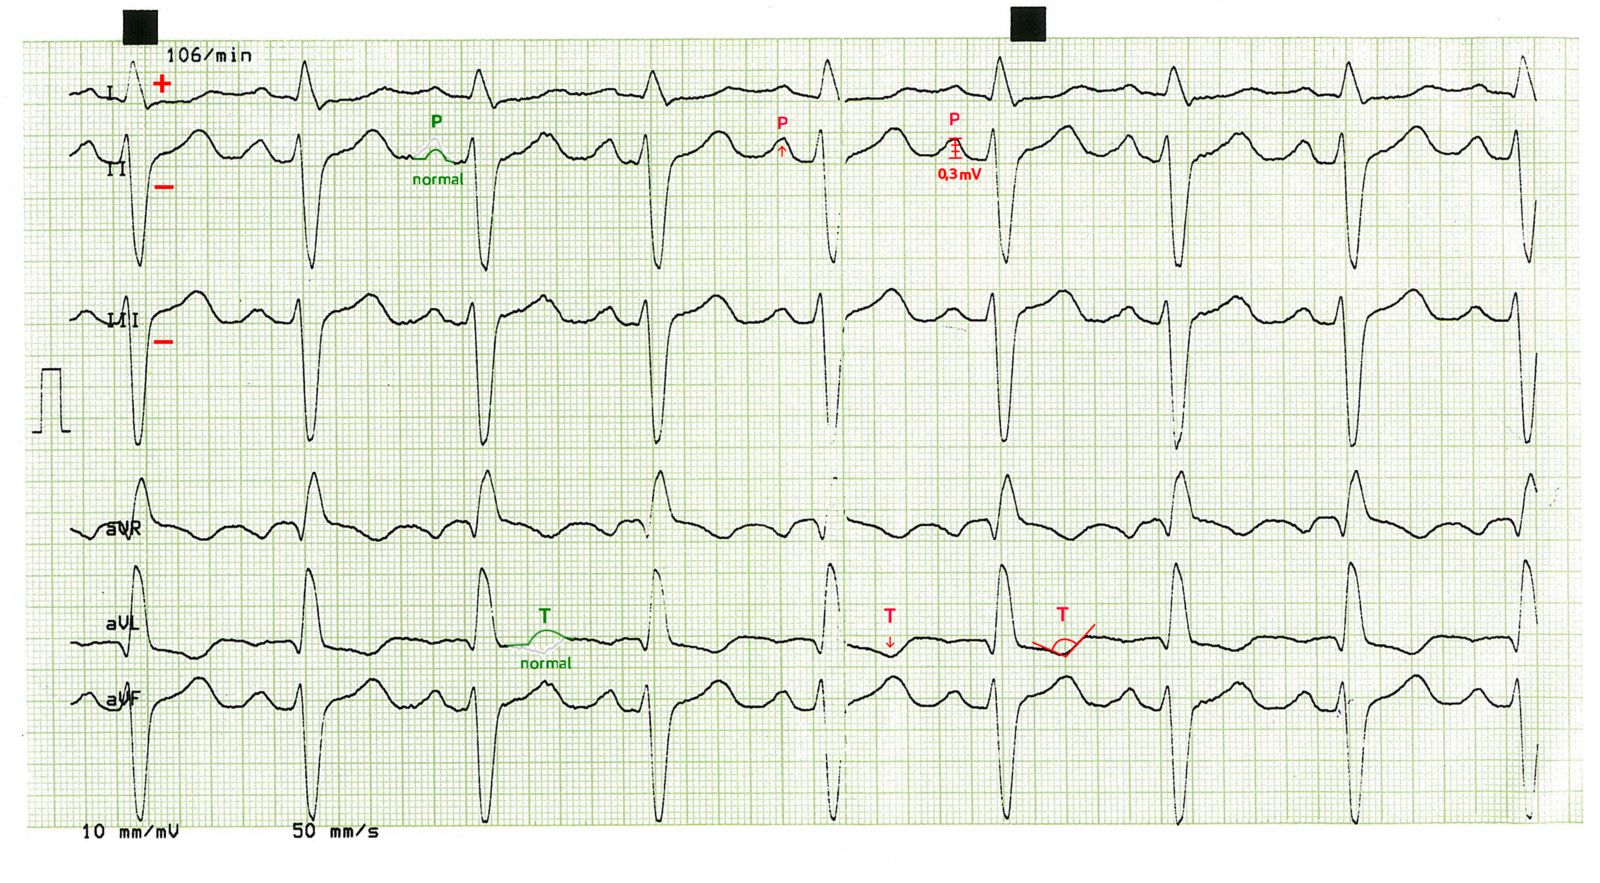

EKG mit Rechtsherzbelastung bei Lungenembolie - 12‑Kanal‑EKG (Papiervorschub 50mm/s)

Tachykarde Herzfrequenz mit ca. 106/min

Sinusrhythmus

überdrehter Linkstyp und S1S2S3-Typ

P-dextroatriale (deutlich in II)

präterminale T‑Negativierung in aVL.